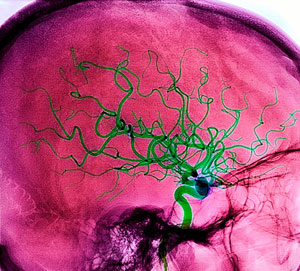

Новые томографы для донецких больниц

В больницах города Донецка появилось уникальное медицинское оборудование, а именно два портативных томографа, позволяющих исследовать головной мозг после инсульта.